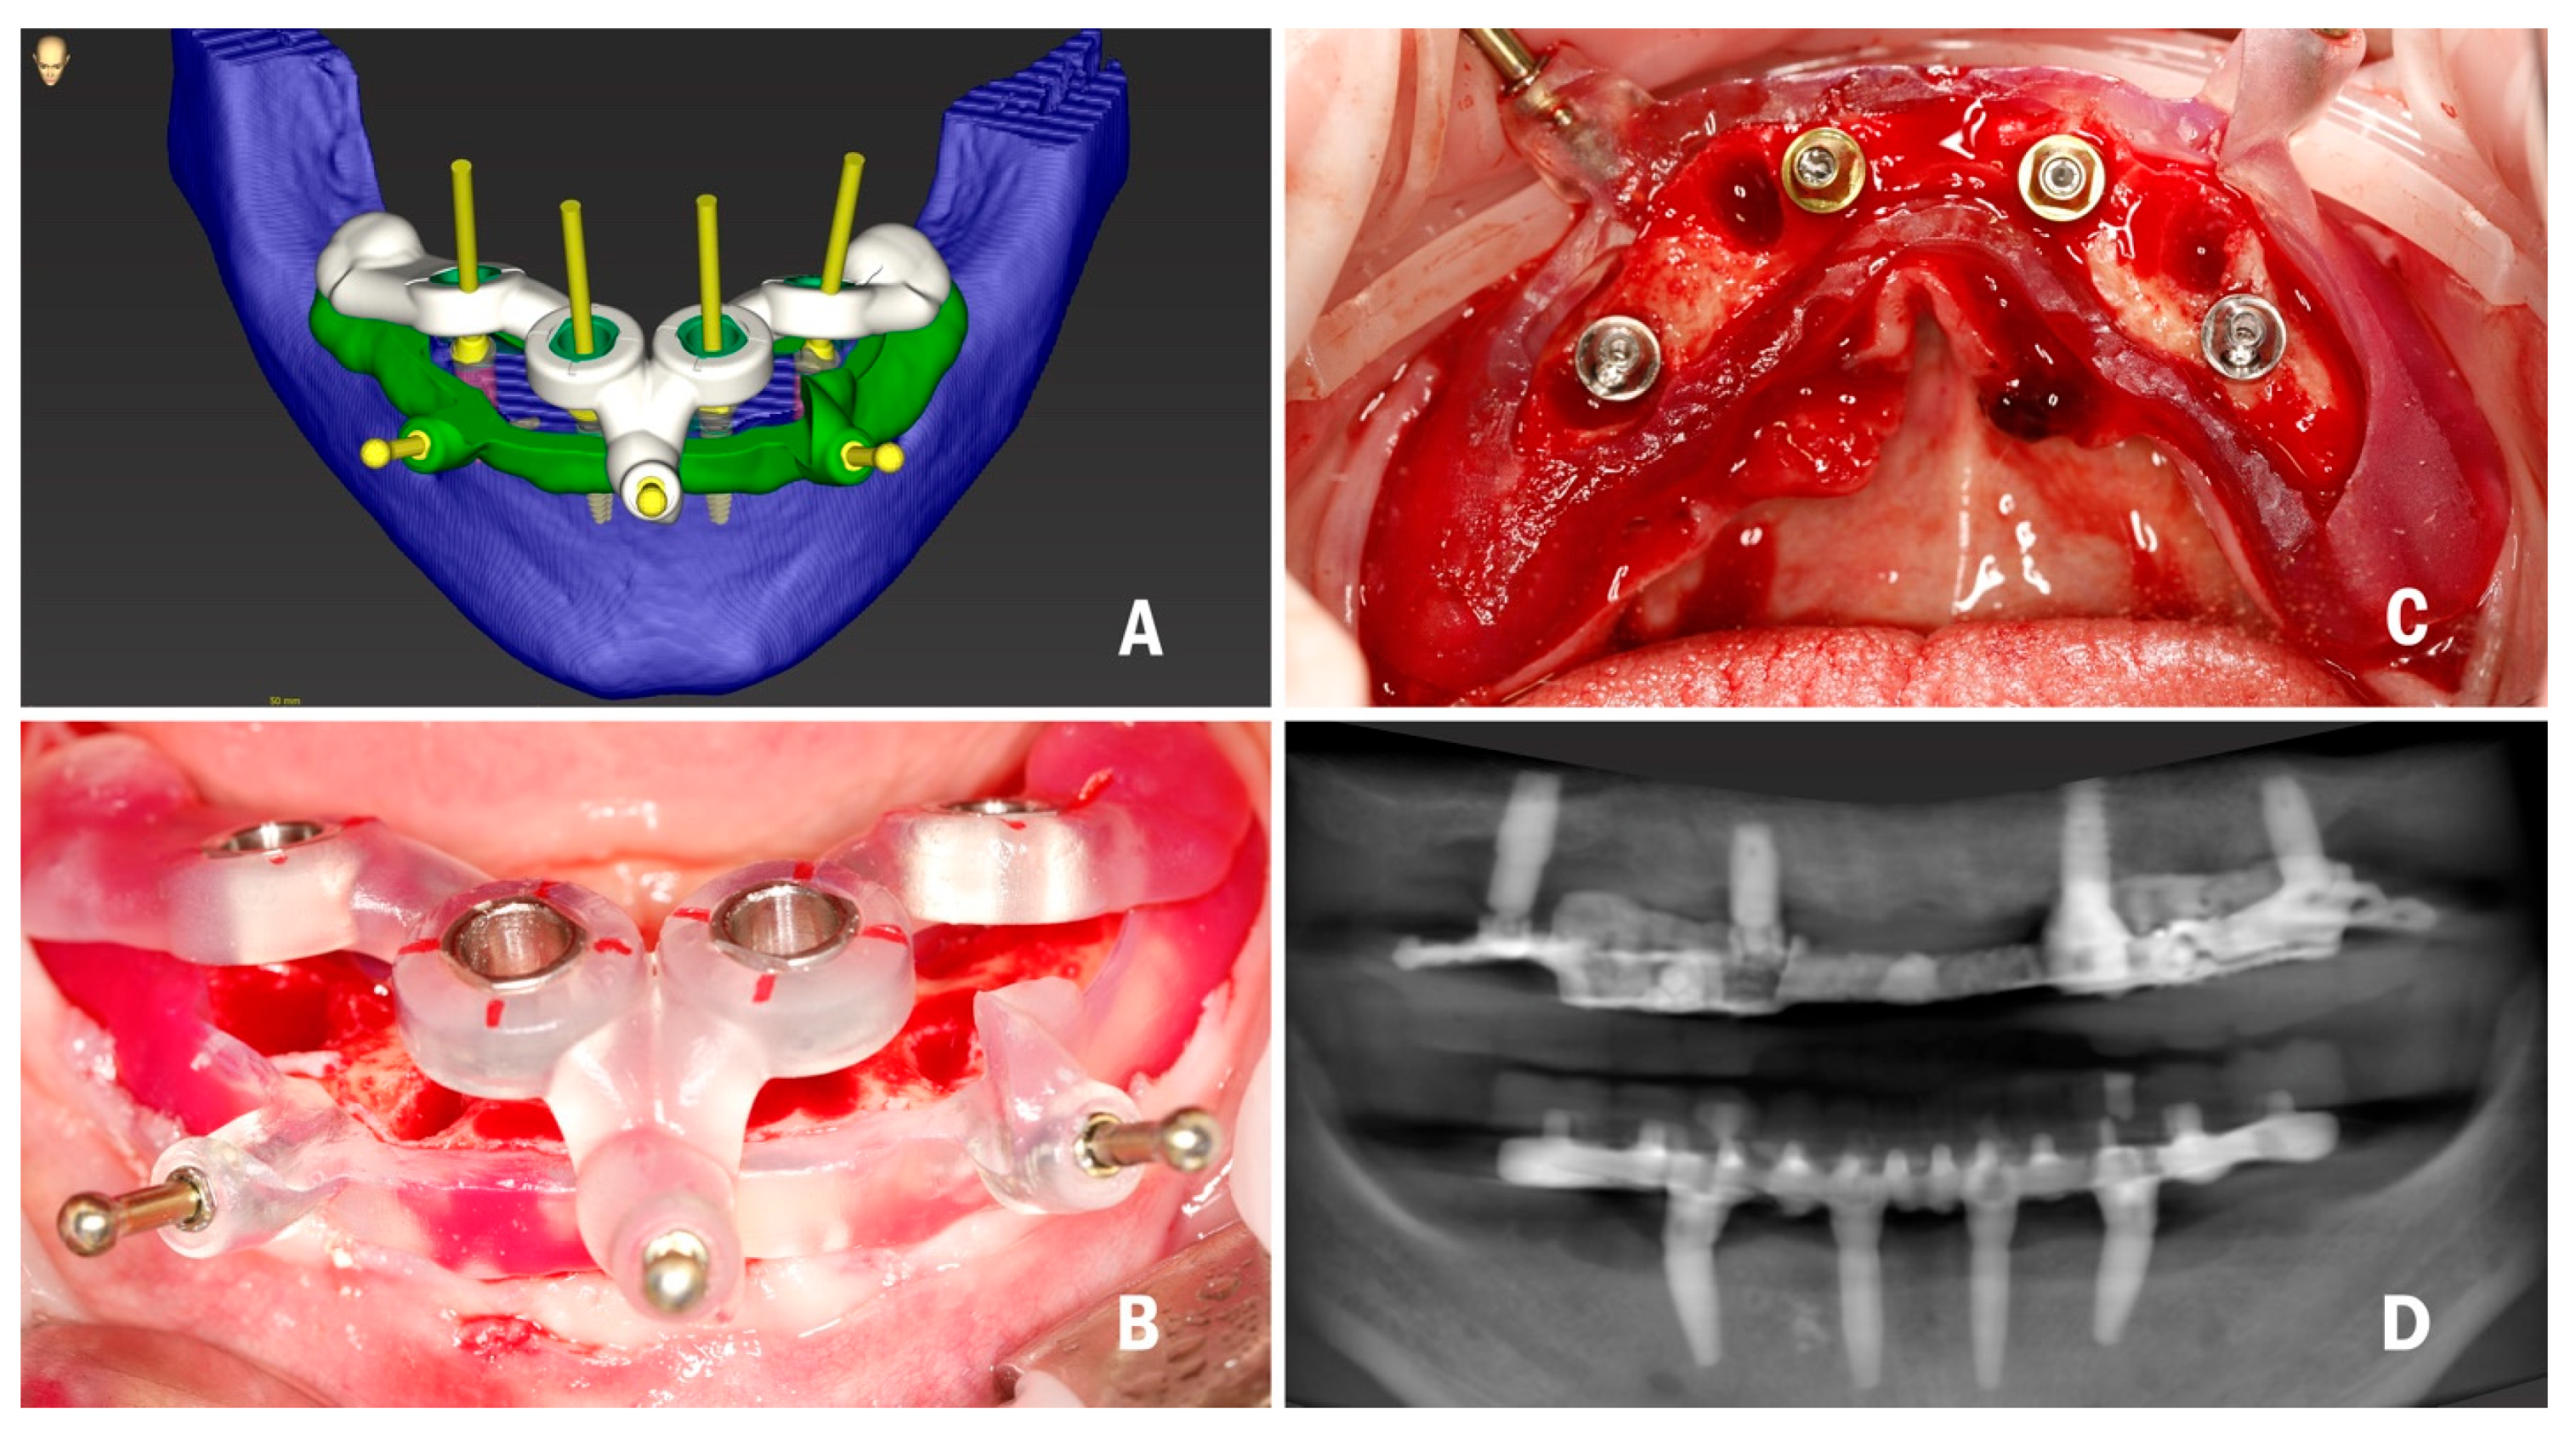

2. Materials and Methods

2.1. Planning and Surgery

3.1. In Vivo Treatment Evaluation